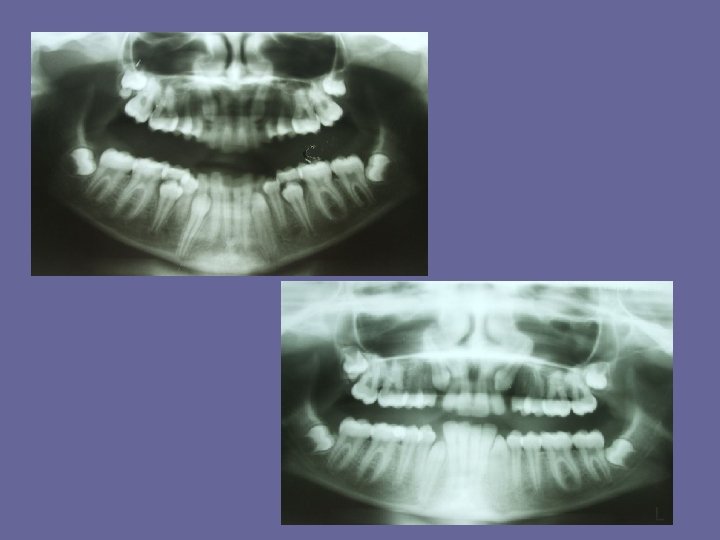

THE MIXED DENTITION • At the age of 6 years permanent teeth, usually the first molars or lower central incisors start to erupt. • As in the case of the deciduous teeth, eruption times are very variable and a range of 18 months on either side is not unusual. • There also some sex differences in the age of eruption. Girls are 1/2 year ahead of boys. • During this century there has been a tendency towards earlier eruption of permanent teeth in the developed countries ( "secular trend" ). It has mainly been due to the earlier onset of puberty, and indirectly to better child health and nutrition

THE MIXED DENTITION Typical ages of eruption: • first molar. . . 6 -7 years • central incisor. . . 6 -7 years • lateral incisor. . . 7 -8 years • canine. . . 9 -13 years • premolars. . . 9 -13 years • second molar. . . 11 -14 years • third molar. . . 17 -30 years The permanent teeth erupt first in mandible and then in maxilla except the premolars which erupt first in maxilla.

THE MIXED DENTITION

THE MIXED DENTITION • At the time of eruption 2/3 of the root is generally formed. Thereafter, 1, 5 -3 years are needed to complete root length and even longer to close the root apices to the mature size.